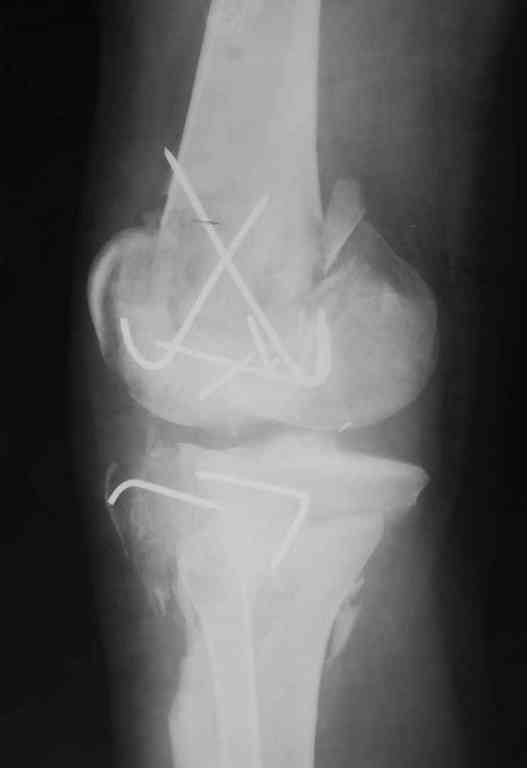

Тамошние доктора выполнили ПХО с удалением фрагментов латерального мыщелка бедра. Наложен АВФ. По возвращению в Украину через 1,5 месяца АВФ демонтирован. И так как смещение фрагментов бедра не устранено, было принято решение после заживление ран от стержней выполнить МОС. Не сколько для четкой анатомической репозиции сколько для подготовки к установке эндопротеза в будущем. Что и было выполнено 10 августа. Интраоперационная картина следующая. Дефицит практически всего латерального мыщелка бедра. Была выполнена попытка закрепить то что осталось от мыщелка, но он развалился на фрагменты. ВЫполнен ситуационный синтез спицами. Дефект заполнили бикортикальным трансплантатом из крыла подвздошной кости, МОС страйкеровским фиксатором. В послеоперационном периоде к 10 дню начались боли, гипертермия. Повышение СОЭ, лейкоцитоз. Посев крови транзиторная бактериемия золотистого стаф. Взяли в операционную. Выполнили дренирование сустава и области п\о раны. Получили гематому фактически с гноем. Температура нормализовалась. Назначили ванкомицин по 1000 мг 2 раза в день.который принимает с 28 августа по сей день. Температура нормальная, СОЭ на убыль. Посевы отделяемого стафилококк 2 ст активности. Но отделяемое по дренажам продолжает идти в достаточном количестве. Взял посев, сеется стаф. 3 ст активноси. К ванкомицину, понятно, слабочувствителен. Что в этой ситуации посоветуете?

Коллеги фиксатор Numelock II

На вашем снимке из-за ротации трудно угадать положение пластины, и желательно сделать снимок с захватом верхнего участка бедра.

Одинокий кортикальный шуруп не удержит тибиальный бугор, сустав тибиал плато оставлен без репозиции и фиксации.